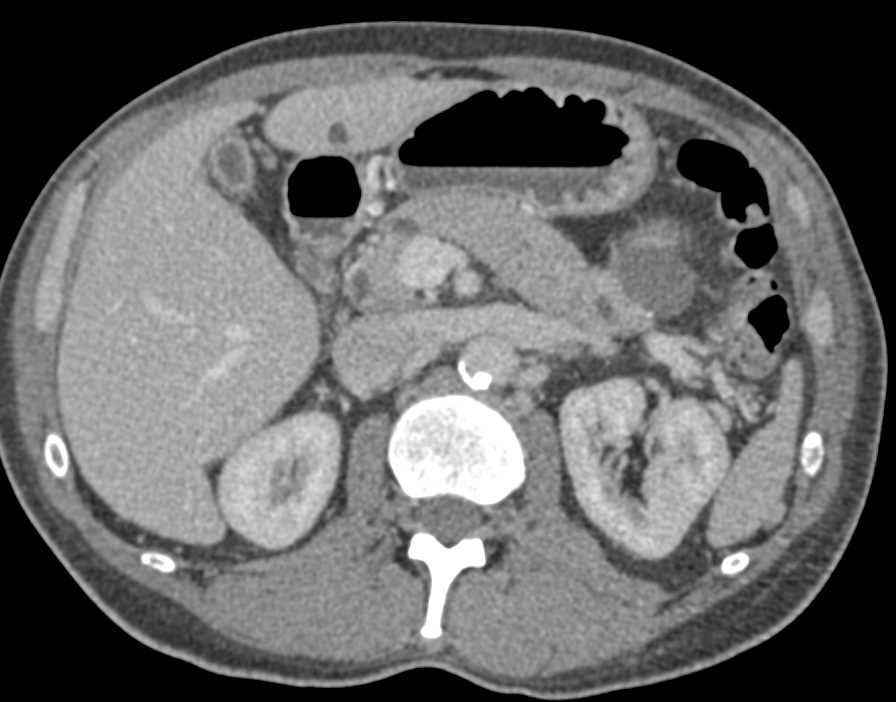

Autoimmune Pancreatitis Involves the Tail of the Pancreas